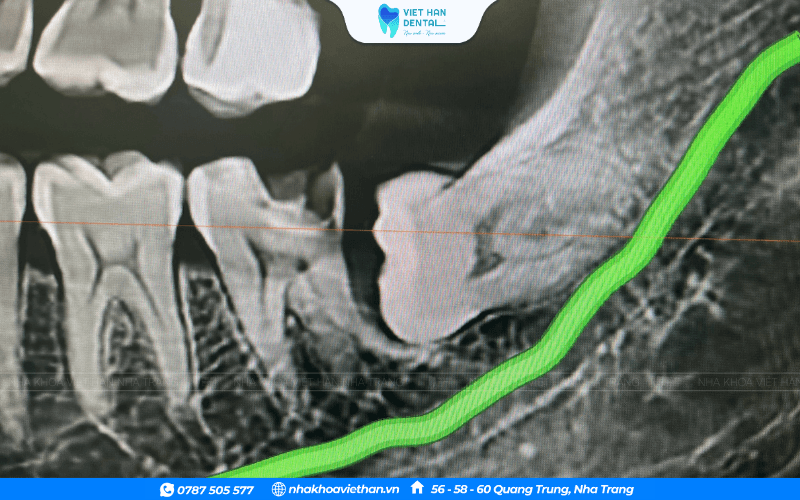

Răng khôn thường có hình dáng và vị trí mọc khác thường so với những chiếc răng còn lại. Chính vì thế mà việc nhổ bỏ răng này cũng gặp nhiều khó khăn hơn. Do đó, nhiều người hiện nay vẫn còn khá e ngại rằng nhổ răng khôn sẽ gây chạm dây thần kinh phía dưới cung hàm.

Răng khôn mọc chèn dây thần kinh

Bao quanh vị trí răng khôn mọc là hệ thống các dây thần kinh hàm mặt. Do đó, nếu răng khôn mọc lệch hoặc mọc ngầm sẽ làm dây thần kinh bị chèn ép. Làm cho người bệnh bị tê bì ở vùng môi, má và lưỡi. Hơn nữa, răng khôn cũng có thể gây ra hội chứng giao cảm như: đỏ quanh ổ mắt, đau một bên mặt.

Trong trường hợp nhổ răng khi răng đã mọc chèn vào dây thần kinh thì sẽ ít nhiều gây ảnh hưởng đến các dây thần kinh xung quanh mặt. Tuy thế, vẫn nên nhổ bỏ đi vì nó giúp bạn ngăn ngừa được nhiều biến chứng nguy hiểm. Không những vậy, bác sĩ cũng sẽ đưa ra phương án điều trị tốt nhất khi răng khôn có dấu hiệu làm tổn hại đến dây thần kinh.